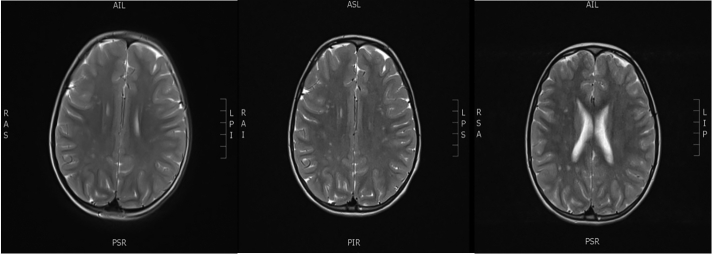

患儿第一次就诊时,黄体生成素(LH)值升高(基础LH 0.2 IU/L,经GnRH 100μg/m2*体表面积刺激后,LH峰值为26.2 IU/L),骨龄显著提前(+3.5 SD),生长速度加快(就诊前6个月,她身高增加了6 cm),证实了患儿的中枢性早熟。此后,她每3个月定期接受GnRH激动剂曲普瑞林治疗,有效地阻止了青春期发育。6岁时,她做了脑部核磁共振以排除性早熟的主要原因。脑部核磁共振扫描显示,T2和FLAIR高强度病变位于半卵圆中心、双侧皮质下额叶白质和额顶叶深部白质,下丘脑和垂体未见明显变化。

9岁时重复脑部核磁共振检查显示双侧额叶皮质下白质和额顶叶深部白质高强度病变。采用阿司匹林保护(100毫克/天)。一年后进一步的脑部核磁共振成像显示先前描述的高强度病变没有明显变化(图1)。